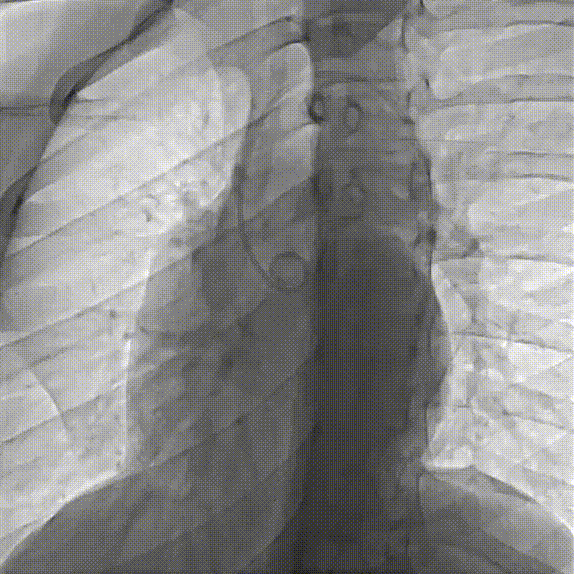

经导管冠状动脉瘘封堵术示意图

A. 经动脉入路。输送系统从瘘管起始口送入释放封堵器。B. 经静脉方法。输送系统从瘘管出口位置送入然后释放封堵器。C. 动静脉环路(AV-LOOP)。用于较大且曲折迂曲的瘘管中,可以借助抓捕器形成AV轨道,以最大限度地支持导管和封堵装置输送。

[引自J Am Coll Cardiol Intv 2021;14:1393–1406]